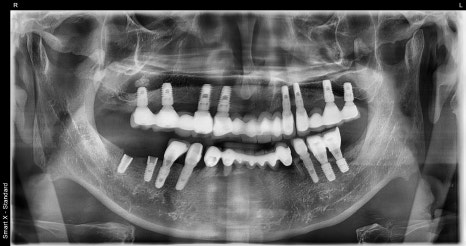

Left photo: A panoramic X-ray taken before treatment. A fractured implant is visible in the lower jaw, and the condition of the existing implant prosthesis can be seen in the upper jaw.

This panoramic X-ray was taken after treatment was completed. The implants had integrated stably and the bite was well adjusted.